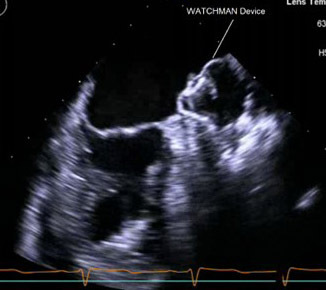

Watchman Left Atrial Appendage Occlusion System

The Watchman LAA system consists of a nitinol cage with a polytetrafluoroethylene membrane on the surface and fixation barbs around the perimeter. The system also contains a transseptal access sheath and a delivery catheter. The Watchman implant is available in diameters of 21 mm, 24 mm, 27 mm, 30 mm, and 33 mm to accommodate multiple unique anatomies. The system is inserted into the femoral vein and delivered to the LAA via atrial transseptal puncture under TEE.38 (See Figures 1 and 2.)

Figure 1. 2D TEE Image of Deployed Watchman Device in Left Atrial Appendage |

![]() |

TEE: transesophageal echocardiography |